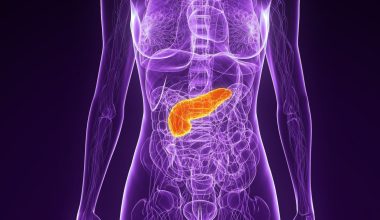

Ελάχιστοι άνθρωποι γνωρίζουν ότι οι πνεύμονές μας δεν είναι δύο αλλά…πέντε. Δεν διαθέτουμε βέβαια πέντε ξεχωριστούς πνεύμονες, αλλά συγκεκριμένα κάθε ένας από τους δύο πνεύμονές μας χωρίζεται σε επιπλέον μέρη, τα οποία ονομάζονται «λοβοί», όπως μας πληροφορεί η σελίδα του Institute of Human Anatomy.

Οι λοβοί των πνευμόνων

Όπως φαίνεται στο βίντεο, ο δεξιός μας πνεύμονας χωρίζεται σε τρεις λοβούς, έναν ανώτερο, έναν μεσαίο και ένα κατώτερο, ενώ ο αριστερός μόνο σε δύο, έναν ανώτερο και έναν, κατώτερο.

Η λειτουργία τους είναι η γνωστή, δηλαδή η απορρόφηση αέρα και η διανομή οξυγόνου στο αίμα και το κυκλοφορικό μας σύστημα. Οι λοβοί των πνευμόνων σχηματίζονται στο ανθρώπινο έμβρυο κατά την κύηση, ξεκινώντας ως κολπώσεις του σπλαχνικού υπεζωκότα που χωρίζουν τους βρόγχους και τέμνουν τους πνεύμονες σε λοβούς, που βοηθά στην επέκτασή τους.

Ωστόσο, ο ακριβής λόγος για αυτό το σχήμα δεν είναι γνωστός, και αποδίδεται στις ιδιαιτερότητες της εξελικτικής διαδικασίας των ειδών. Οι πνεύμονες προγονικών ειδών που εξελίχθηκαν από ψάρια ήταν επιμήκη όργανα με πολύ πιο απλοϊκή δομή.

Είναι πιθανό, καθώς το ζωτικό σύστημα των οργανισμών γινόταν όλο και πιο εξεζητημένο μέσα σε εκατομμύρια χρόνια εξέλιξης, τα υπόλοιπα όργανα να ανάγκασαν τους πνεύμονες να «διπλωθούν» στις μορφές με τις οποίες εντοπίζονται σήμερα.